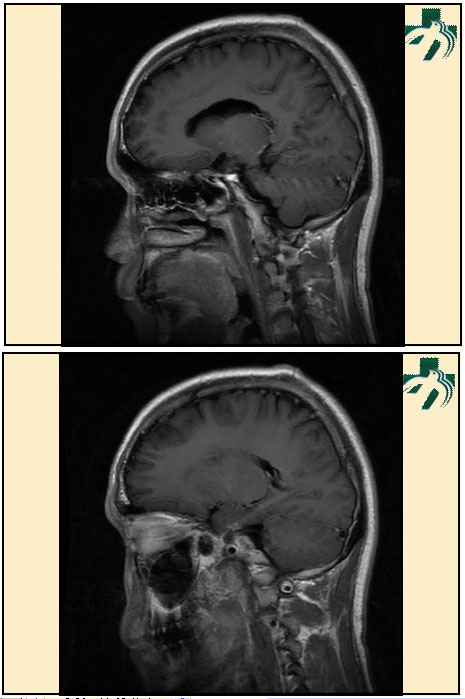

奴卡氏菌感染

第九期三博

读片会

病例之四

北京协和医院 提供

男性,22岁。自觉虫咬后皮疹、肢体麻木4月